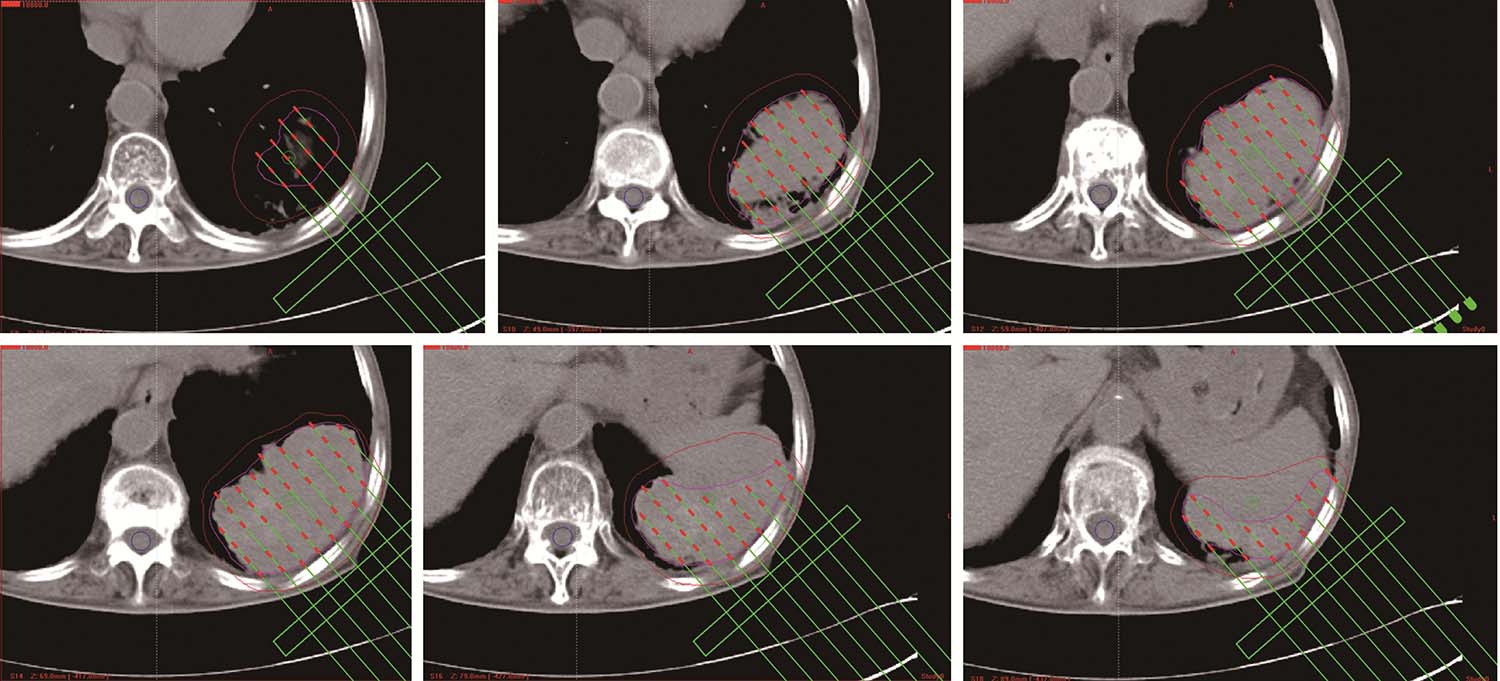

所有患者术前3天行强化CT扫描,依据病灶部位采取仰卧、俯卧、侧卧等体位,真空负压垫固定。拷贝DICOM格式CT图像传输至近距离TPS设计术前计划,临床医生与物理师共同勾画肿瘤靶区体积(GTV)和邻近危及器官(OAR),设定处方剂量和粒子活度,根据病灶位置及与周围重要脏器的关系,设计进针路线,模拟粒子空间分布,确定粒子间距及排布方式,计算粒子数目,计算GTV及OAR的照射剂量,得出剂量体积直方图(DVH)及逐层等剂量分布图。

患者取与术前CT扫描相同体位,真空负压垫固定体位,防止穿刺过程中因体位变动给穿刺带来的不利影响。将导航支架与CT碳纤维床板相连接,以0.5cm层厚扫描,选取病灶中心层面,将一个预定进针点在皮肤表面做出大十字标记,消毒、铺巾、局麻,安装模板,用激光灯校准模板,使激光灯的 x 轴和 y 轴投影与模板表面的标记线相重合,利用数字化角度仪或者水平仪调整模板的角度和方向,使模板在 y 轴方向的角度为零,调整 x 轴方向的角度,与术前计划保持一致。选择病灶中心层面,参考术前计划,将数根穿刺针抵达皮肤表面,扫描观察针尾走行方向,再次校准模板,然后测量进针的深度,完成该层面的进针,如果是肺等移动度较大的脏器,可以先插入2~3根固定针,将病灶与模板迅速“绑定”(图4-3-1),然后再依次完成其他层面的进针,如果遇到坚韧骨骼遮挡,使用捻针或骨钻打孔技术破骨插植,待完成所有层面的进针以后再植入粒子。

测量各层面的进针深度,依据术前计划逐层植入粒子,在拔除穿刺针之前,再次行CT扫描,仔细观察粒子的分布情况,如果发现粒子聚拢或者移位,即刻进行补种。术毕即刻大范围扫描,进行术后剂量评估。

将术后即刻扫描得到的图像传入TPS行术后验证计划,勾画靶区、危及器官,识别粒子,得出等剂量曲线分布及剂量体积直方图。GTV剂量学参数包括D 90 、D 100 、V 90 、V 100 、V 150 、V 200 ,以适形指数(CI)评价剂量分布的适形度,以靶区外体积指数(EI)描述靶区外接受超过处方剂量体积占靶区体积的百分比,以均匀性指数(HI)用于评价剂量分布均匀性。

图4-3-7 术后等剂量分布图

图4-3-11 术后等剂量分布图

图4-3-12 术后粒子分布三维重建图